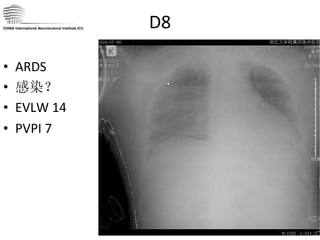

D8 ARDS 感染? EVLW 14 PVPI 7 CHINA International Neuroscience Institute ICU

D8 ARDS 感染?EVLW 14 PVPI 7 CHINA International Neuroscience Institute ICU

D8  高循环状态和肺水 治疗上出现矛盾 ICP 虽较前明显降低, 20-30mmHg (正常 <15 ),但由于脑血管痉挛,有效脑灌注脑电活动下降,支持脑灌注压力仍大,为保证脑循环需要持续高 CO  状态。 但肺水持续增高, ALI ? CHINA International Neuroscience Institute ICU

D8 高循环状态和肺水治疗上出现矛盾 ICP 虽较前明显降低, 20-30mmHg (正常 <15 ),但由于脑血管痉挛,有效脑灌注脑电活动下降,支持脑灌注压力仍大,为保证脑循环需要持续高 CO 状态。 但肺水持续增高, ALI ? CHINA International Neuroscience Institute ICU